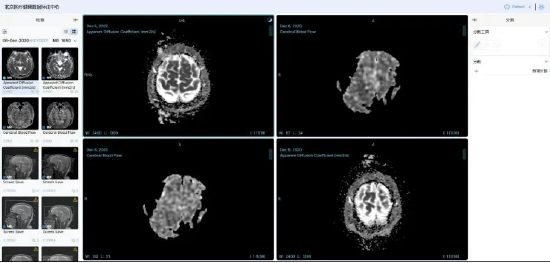

中国联通联合国内多家顶尖医疗机构,构建了覆盖影像、诊疗、药品等全维度的高质量数据集,其中,数据集总规模达100TB,胸部CT影像数据集标注2万余例,肺结核辅助诊断模型准确率超95%;耳部CT影像数据集标注5000余例,听觉障碍识别准确率达95%;肾脏病慢病管理数据集整合1万例患者全周期数据,风险预警模型准确率突破95%;药品说明书数据集涵盖58000份药品信息,实现用药风险智能解析与动态评估。

在数据治理与管理方面,联通数智公司构建医疗健康行业可信空间,制定数据脱敏规范,运用数据沙箱和隐私计算双引擎处理数据,确保“原始数据不出域、数据可用不可见”。建立11项数据治理全流程运营标准,通过多维度举措保障数据质量与安全。例如,在胸部CT影像数据标注中,采用双盲标注和专家抽样审核,确保标注一致性评估结果超95%,准确性达98%以上。

基于该高质量数据集,中国联通研发了一系列医疗专科智能体。基于胸部CT影像的肺结核疾病筛查与诊断模型智能体,准确率超 95%,可实现分钟级快速检测;肾脏病慢病管理干预模型智能体、耳部疾病辅助诊断模型智能体,助力医务人员提高诊断效率及诊疗方案准确性;药品全生命周期智能评估模型智能体,为药品研发、监管等提供全链条数据支撑。